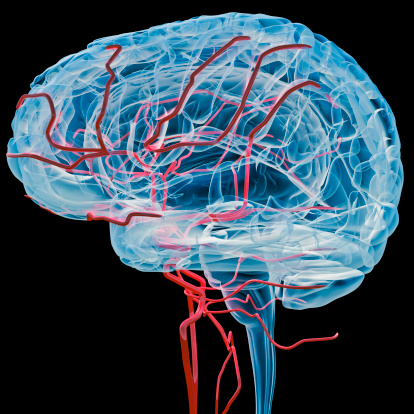

Probiotics improve depression symptoms